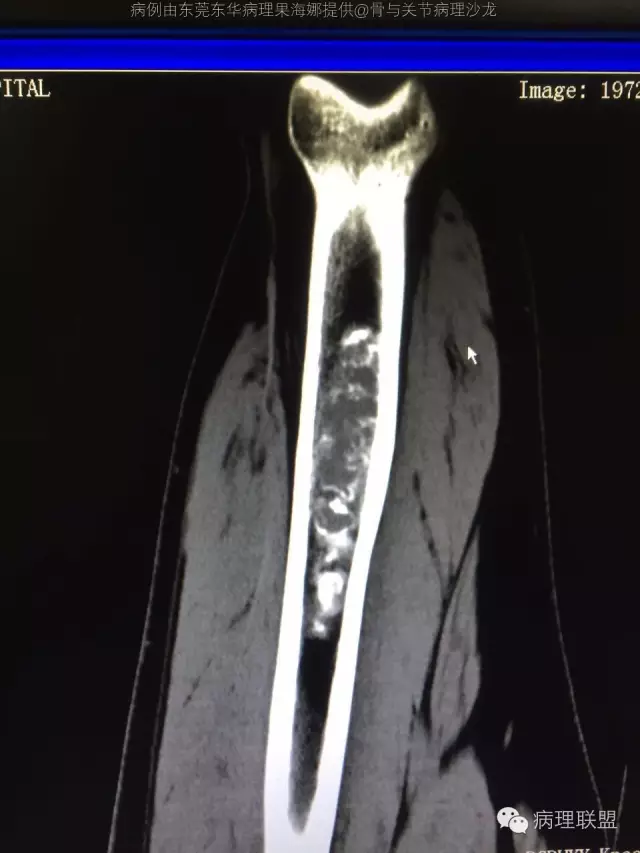

@东莞东华病理果海娜 ,组织学异型不明显,灶性粘液变,骨包软骨,但影像第二张显示可疑皮质侵犯,肿瘤体积较大,故考虑不典型软骨性肿瘤/软骨肉瘤I级

@中山大学附一院病理李扬 我看不太好皮质侵犯,就觉得长轴太长了

@张惠箴上海六院 这张能说明软骨肿瘤侵犯松质骨吗?这两张能理解成软骨周围有宿主对软骨肿瘤的纤维反应吗?

建议你再多取一点材,这张照片不是很典型,也许不是显微镜下看,有差异小叶软骨周围至少不像骨包绕@东莞东华病理果海娜